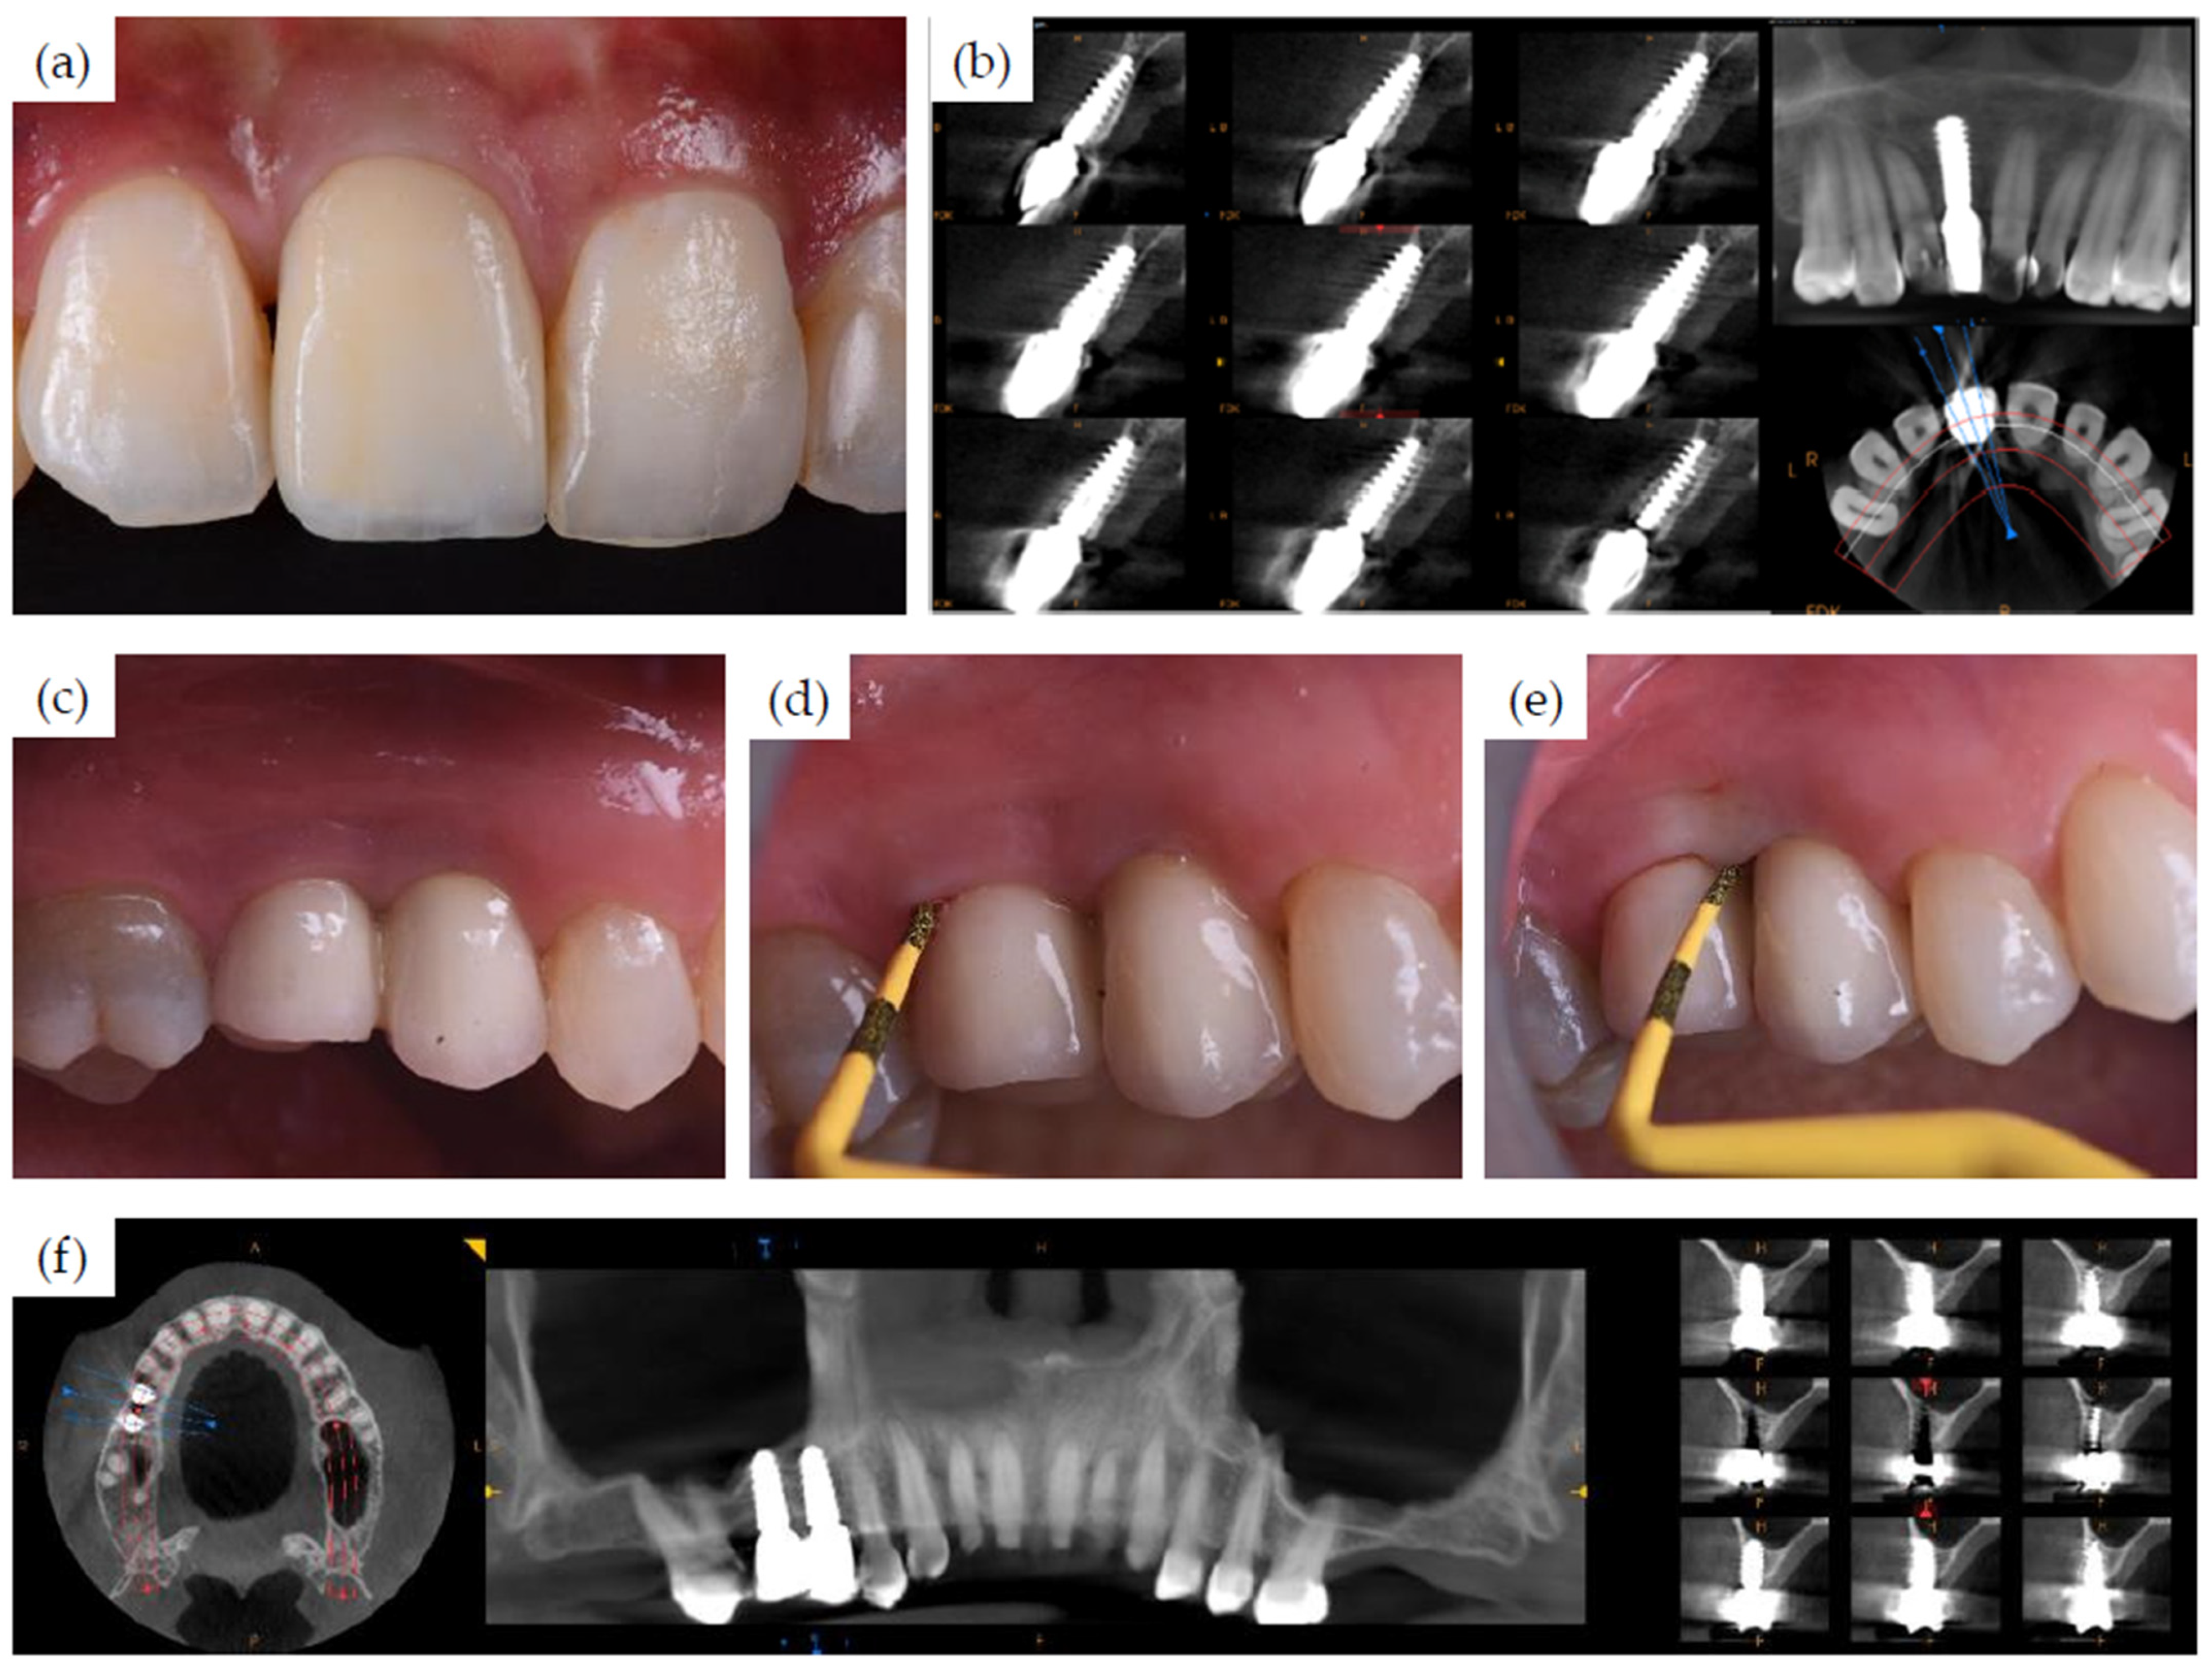

3.1. Clinical Cases

| 1 | 38 | female | 11 | 3, B | buccal concavity | healed | Not reported | 45 | yes |

| 2 | 47 | female | 15 | 4, C | Sinus lift | healed | Not reported | 45 | no |

| 16 | 4, C | Sinus lift | healed | Not reported | 45 | no | |||

| 3 | 58 | female | 12 | 4, B | buccal concavity | recent extraction (12 weeks) | 40 * | 61 | yes |

| 14 | 4, B | - | healed | 10 | 25 | no | |||

| 22 | 4, B | large concavity | healed | 40 * | 39 | yes | |||

| 37 | 4, B | - | healed | 19 | 55 | no | |||

| 38 | 4, B | - | extraction | 5 | 50 | yes | |||

| 4 | 64 | female | 46 | 2, C | narrow ridge | healed | 34/21 ** | 60 | no |

| 5 | 60 | female | 46 | 2, C | - | healed | 23 | 50 | yes |

| 47 | 3, D | - | healed | 21 | 50 | yes | |||

| 36 | 3, B | - | healed | 16 | 37 | no | |||

| 37 | 3, B | - | healed | 16 | 31 | no | |||

| 6 | 18 | male | 21 | 3, B | large concavity, 6 mm lingual defect | healed | 35 | 55 | yes |

| 7 | 26 | male | 36 | 3, B | buccal concavity | healed | 38 | 55 | no |